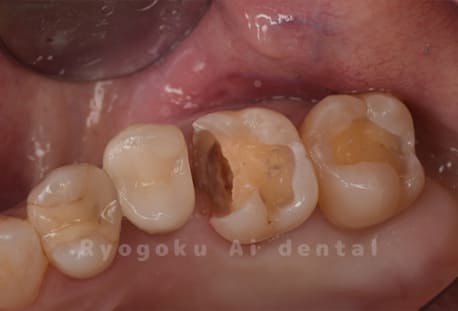

Case10

-

- 原因

- インレー2次カリエス、コンタクトカリエス

- 治療内容

- セラミックインレー、ダイレクトボンディング

- 治療費用

- 77,000円+66,000円

銀歯の部分が噛むと違和感があるとのことで来院されました。右上4番5番の歯の治療をセラミックインレーとダイレクトボンディングで治療した症例です。

<リスク・副作用>

過度の咬合や衝撃で割れることがあります。